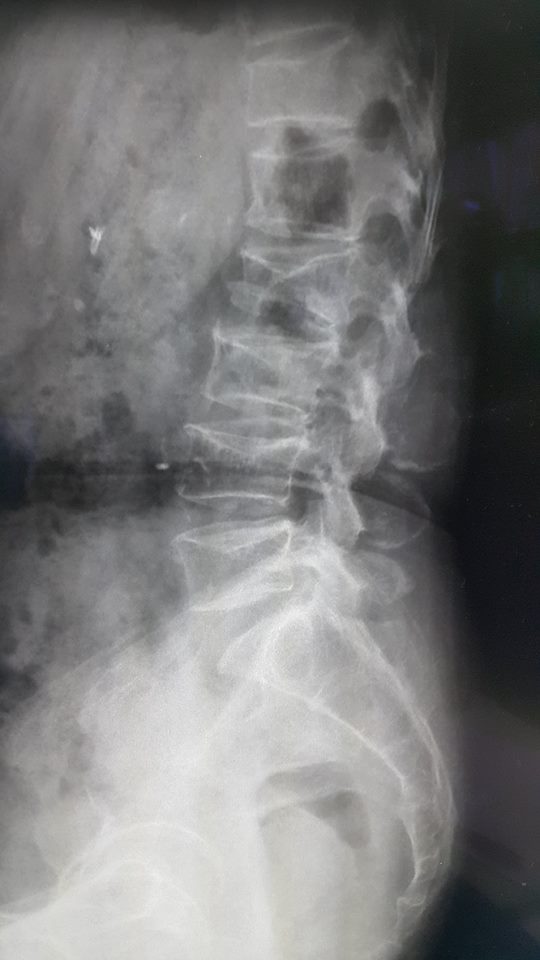

ภาพ MRI แสดงการกดทับของไขสันหลังจากโรคมะเร็ง และภาพเอกซเรย์แสดงการยุบตัวของกระดูกสันหลังจากโรคกระดูกพรุน